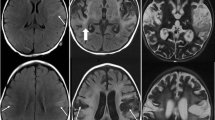

Neuroimaging is another critical diagnostic tool for HSE. Magnetic resonance imaging (MRI) is the preferred modality, with abnormalities seen in over 90% of PCR-proven cases. In resource-limited settings where MRI is difficult to obtain, computed tomography (CT) may be considered, though sensitivity is much lower, especially early in the disease course [12]. The most frequent MRI finding is unilateral or bilateral T2 hyperintensity within the temporal lobes, though frontal lobe involvement is also quite common. The lesions may demonstrate heterogeneous contrast enhancement, diffusion restriction, and/or hemorrhage [12, 20].

CMV has variable seroprevalence with rates around 60% in the developed world and 100% in the developing world [86, 87]. Like EBV, it is rarely associated with neurologic manifestations in the immunocompetent host [5]. Primary infection is usually asymptomatic, followed by viral latency within the bone marrow hematopoietic progenitor cells [88]. Reactivation is generally limited to profoundly immunocompromised hosts, particularly those with advanced human immunodeficiency virus (HIV) infection or following hematopoietic stem cell transplantation (HSCT) [5, 89•]. CMV encephalitis has also been rarely reported in immunocompetent infants [90]. Patients often present with a subacute encephalitis and may have simultaneous retinitis, myelitis, and/or polyradiculitis [5, 89•]. MRI abnormalities are seen in one third of patients with CMV encephalitis, with the most common abnormalities being findings suggestive of ventriculitis (periventricular hyperintensities, subependymal enhancement, diffusion-restricting intraventricular material) [89•]. Diagnosis is made by positive CSF CMV PCR, and CSF may notably have polymorphonuclear pleocytosis and hypoglycorrhachia [89•]. The optimal treatment is unknown, but many advocate for treatment with ganciclovir, foscarnet, or both [5, 91]. Despite treatment, the prognosis of CMV encephalitis is generally poor [5].